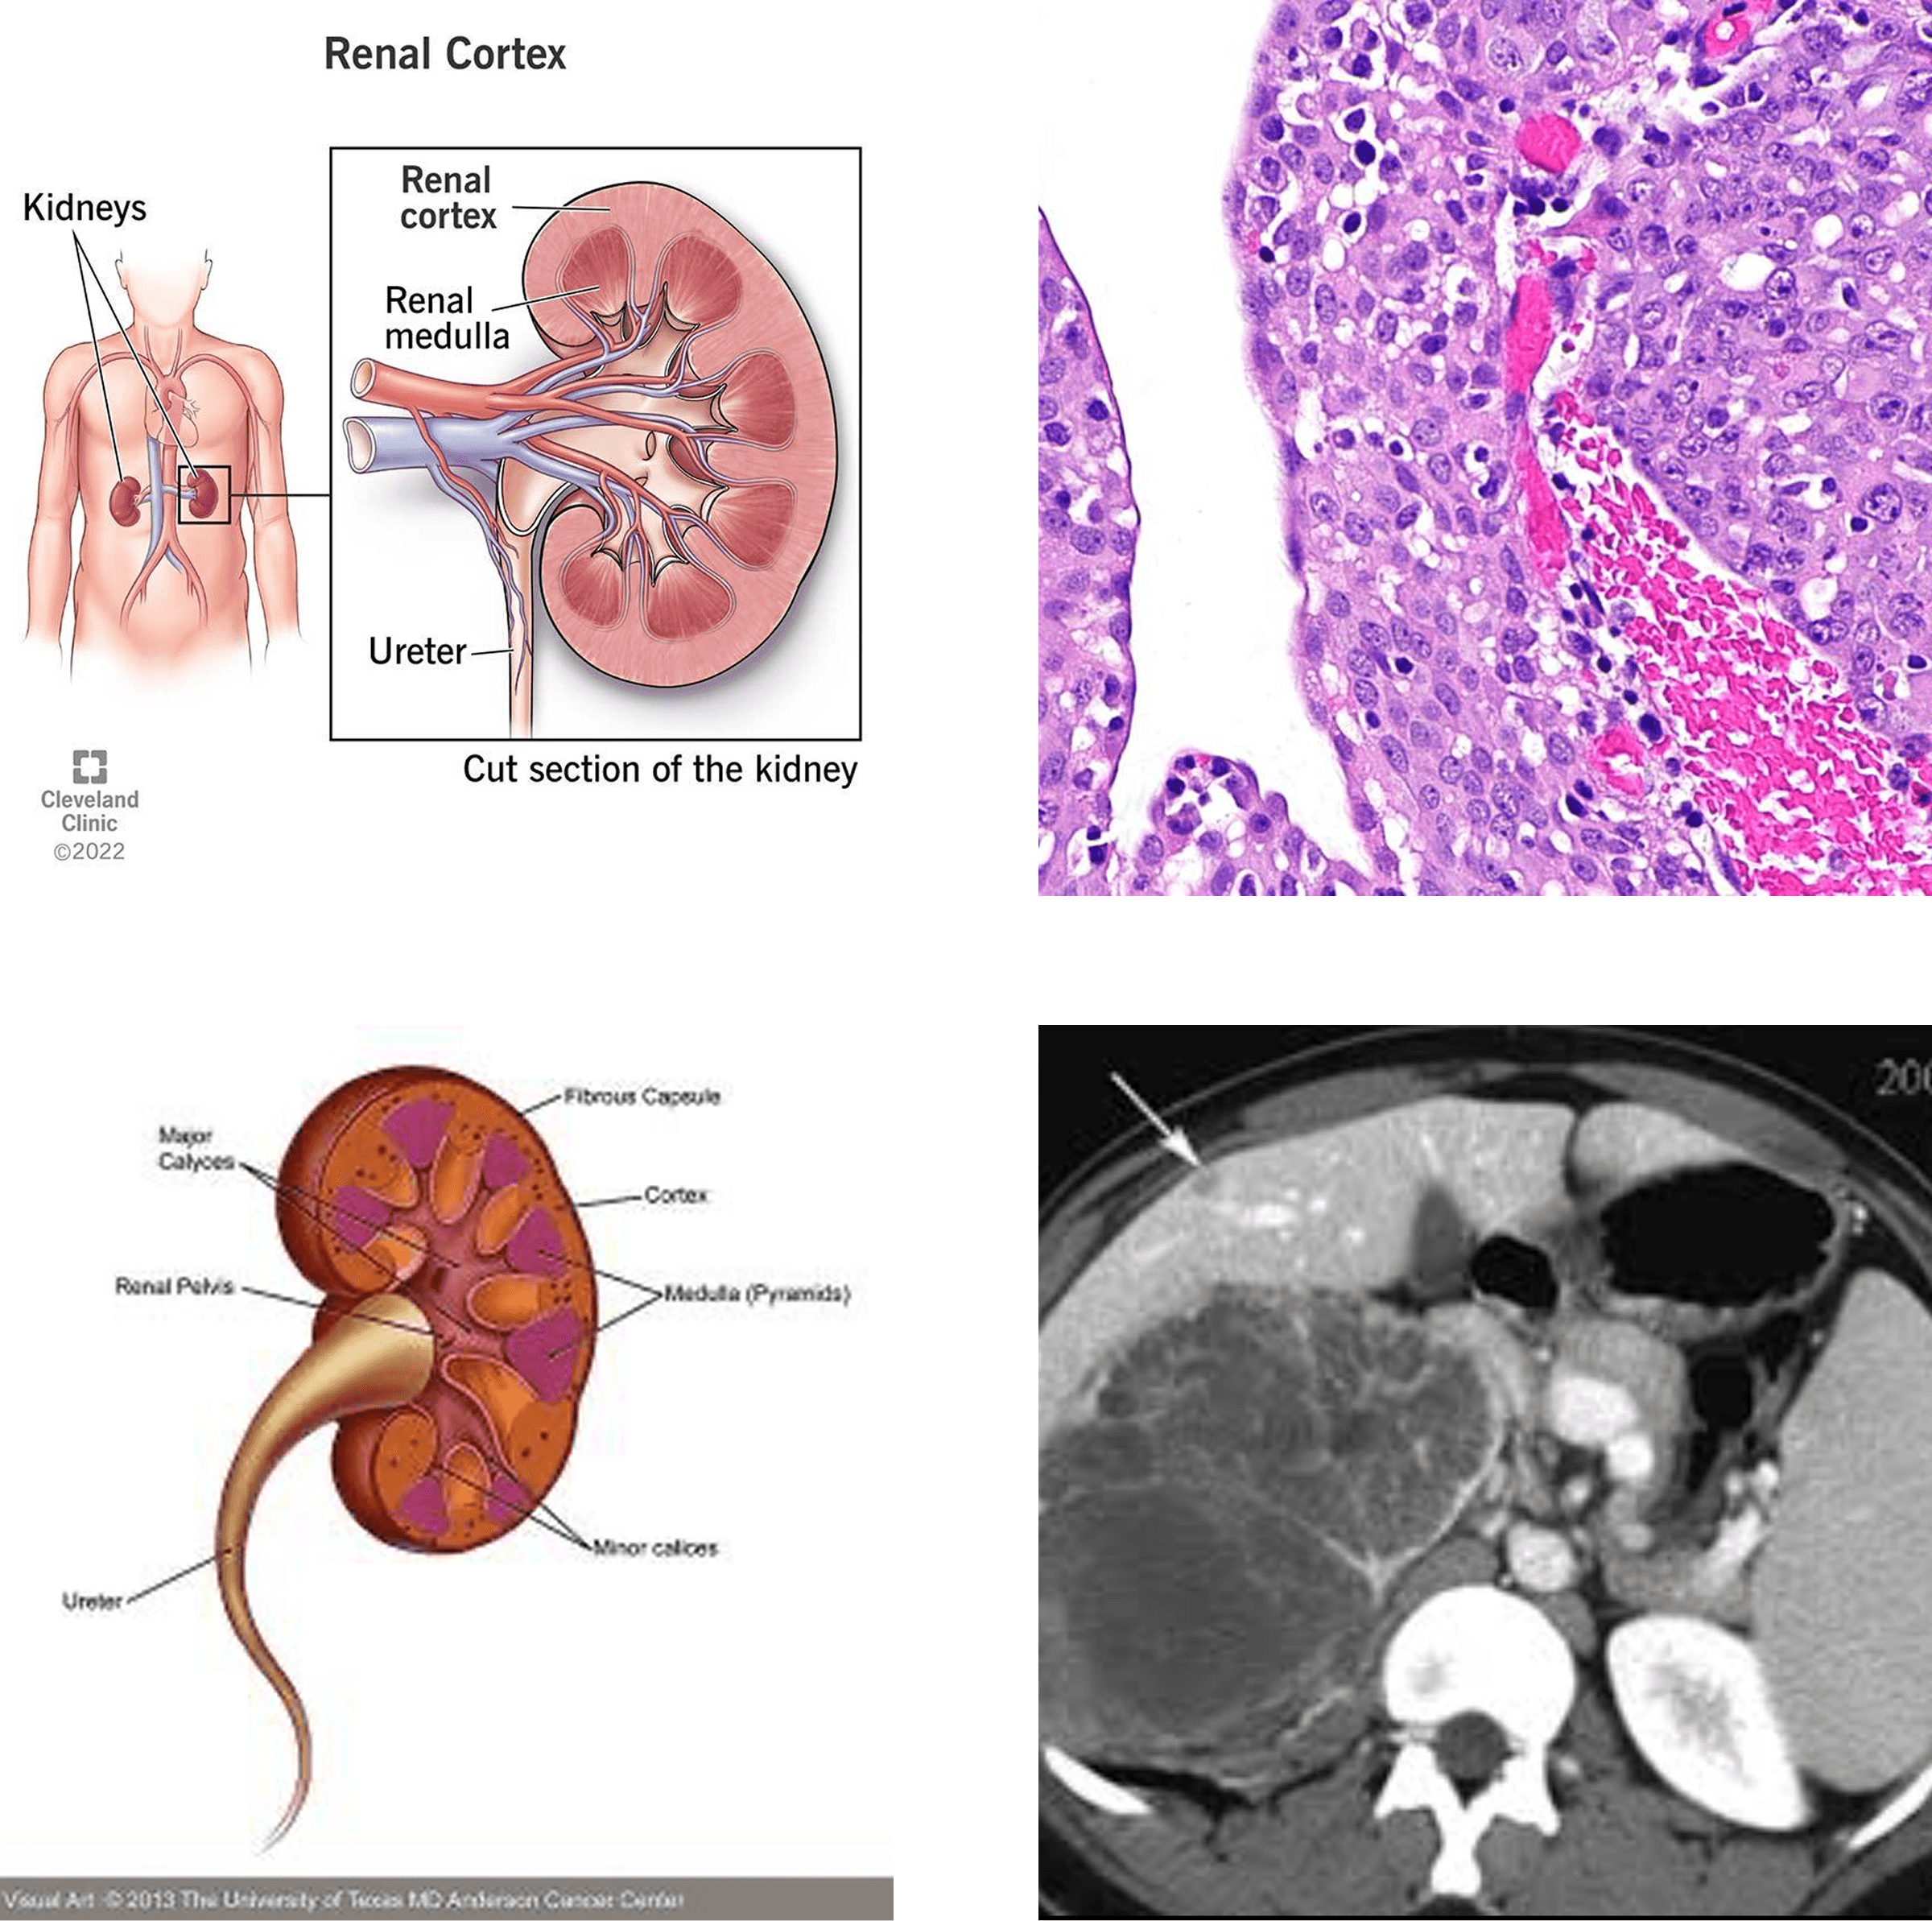

Renal Medullary Carcinoma (RMC) is a rare and highly aggressive form of kidney cancer. It most often affects young individuals, particularly those with sickle cell trait. Because it progresses rapidly and is difficult to detect early, RMC is often diagnosed at advanced stages.

How is RMC Diagnosed?

Diagnosis typically involves:

- Imaging studies such as CT scans or MRIs

- Biopsy of the kidney tumor

- Specialized pathology testing

Because RMC is rare, diagnosis may require evaluation by specialists familiar with the disease.